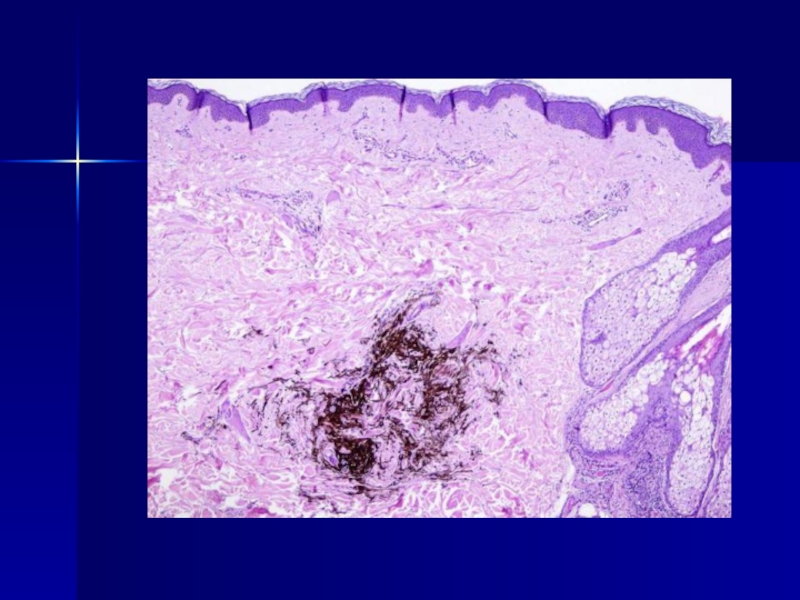

Слайд 12Невус Шпитц

Невус Шпитц

Слайд 13Невус Шпитц (ювенильный невус)

Невус Шпитц (ювенильный невус)